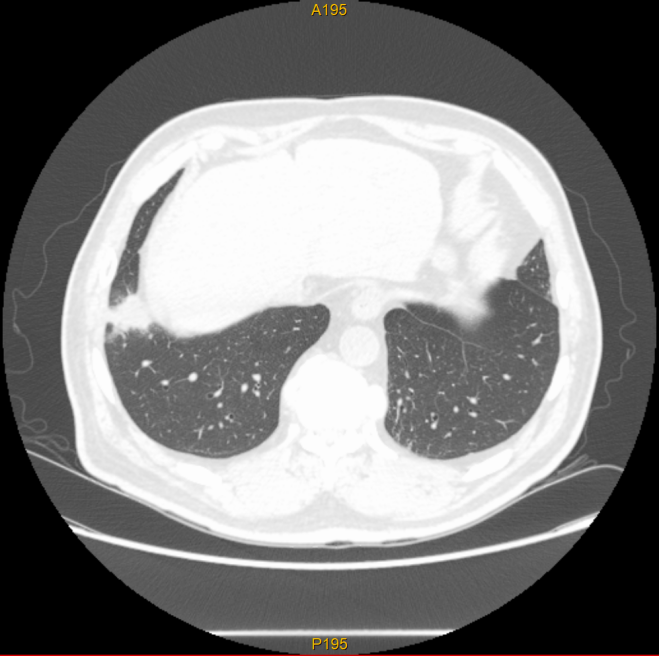

近日,我院肿瘤放射治疗科应用体部立体定向放疗(SBRT)技术,为一名胆管癌肺转移患者实施了精准放射治疗。通过制定规范的放射治疗计划,肺部两个转移病灶在接受SBRT治疗后基本消失,复查影像显示肿瘤已得到良好控制,彰显了精准放疗技术在肿瘤治疗中的独特优势。

该患者为胆管癌术后出现肺转移,两个转移病灶分别位于右肺上叶后段(大小26*25mm)及右肺下叶前基底段(大小28*30mm)。此前,患者已接受肝动脉化疗灌注(HACI)及多疗程全身化疗,但肺部病灶仍有增大趋势,治疗一度陷入困境。

治疗过程非常顺利,患者无明显不适。治疗结束后复查,两个肺部转移病灶已基本消失,显示出SBRT在局部肿瘤控制方面的绝对优势。这一结果不仅为患者带来了新的希望,也再次印证了精准放疗在肿瘤综合治疗中的重要地位。